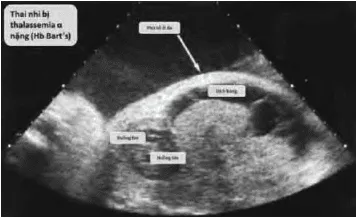

- Mất 4 gene α (Hb Bart’s, thai phù): Không có chuỗi α; Chỉ có chuỗi γ với ái lực O₂ cao → thai phù đa màng, suy tim, tử vong thường từ tuần 30 đến ngay sau sinh.

- Thể nặng có thể không sống sót sau sinh.

- Cân nhắc tư vấn chấm dứt thai kỳ nếu phát hiện Hb Bart’s.